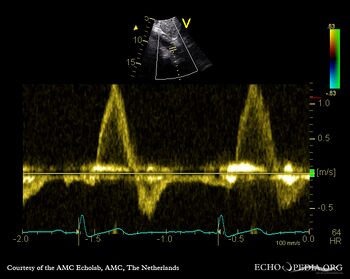

E00857.gif

A5CH Continuous-wave Doppler signal of severe aortic regurgitation